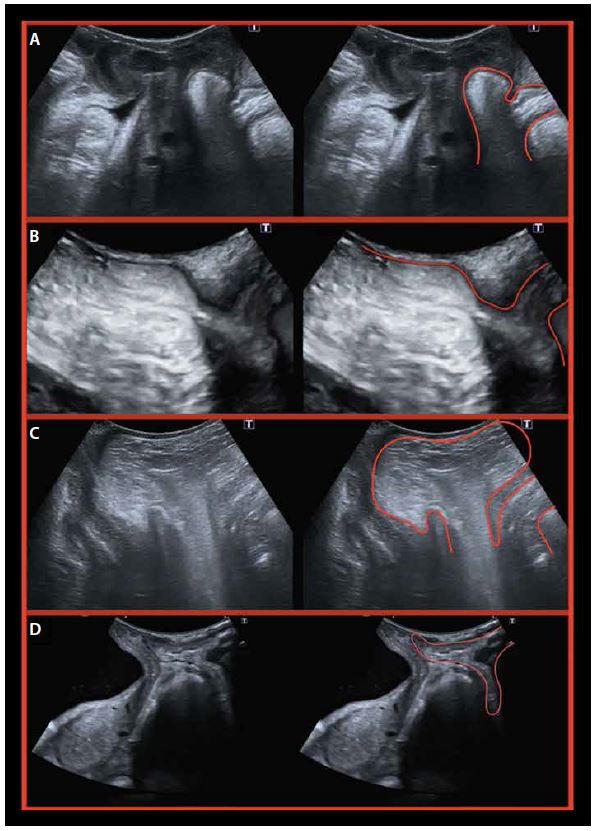

Ультразвукову диференційну діагностику патології заднього відділу необхідно проводити з перевіркою:

• Ректоцеле: грижа передньої стінки прямої кишки у напрямку до піхви (мал 8A).

• Ректоентероцеле: грижа ректоцеле поєднується з грижею тонкої кишки або іншого вмісту черевної порожнини у напрямку до піхви (мал. 8B).

• Ентероцеле: випинання вмісту черевної порожнини в напрямку аноректального кута, що відокремлює піхву від ампули прямої кишки (мал. 8C).

• Ректальна інвагінація: інвагінація передньої стінки прямої кишки в анальний канал на рівні кута аноректального каналу (мал. 8D).

Малюнок 8. Ультразвукова диференціальна діагностика заднього відділу: ректоцеле (A), ректоентероцеле (B), ентероцеле (C), ректальна інвагінація (D).